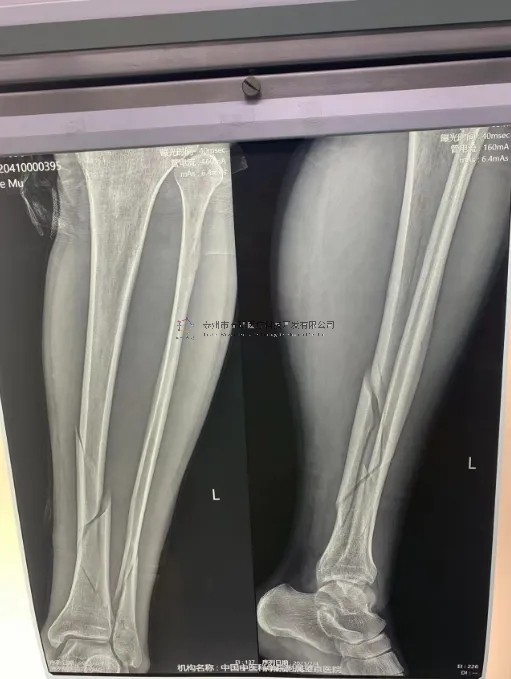

典型病例

2月份,我們在中國中醫(yī)科學(xué)院望京醫(yī)院就有多臺關(guān)于外固定支架的手術(shù),以下介紹一則不開刀CO接骨治療小腿骨折典型病例:

【所屬科室】創(chuàng)一

【基本資料】患者,男,43歲

【患者情況】左脛腓骨近端骨折

【影像圖片】